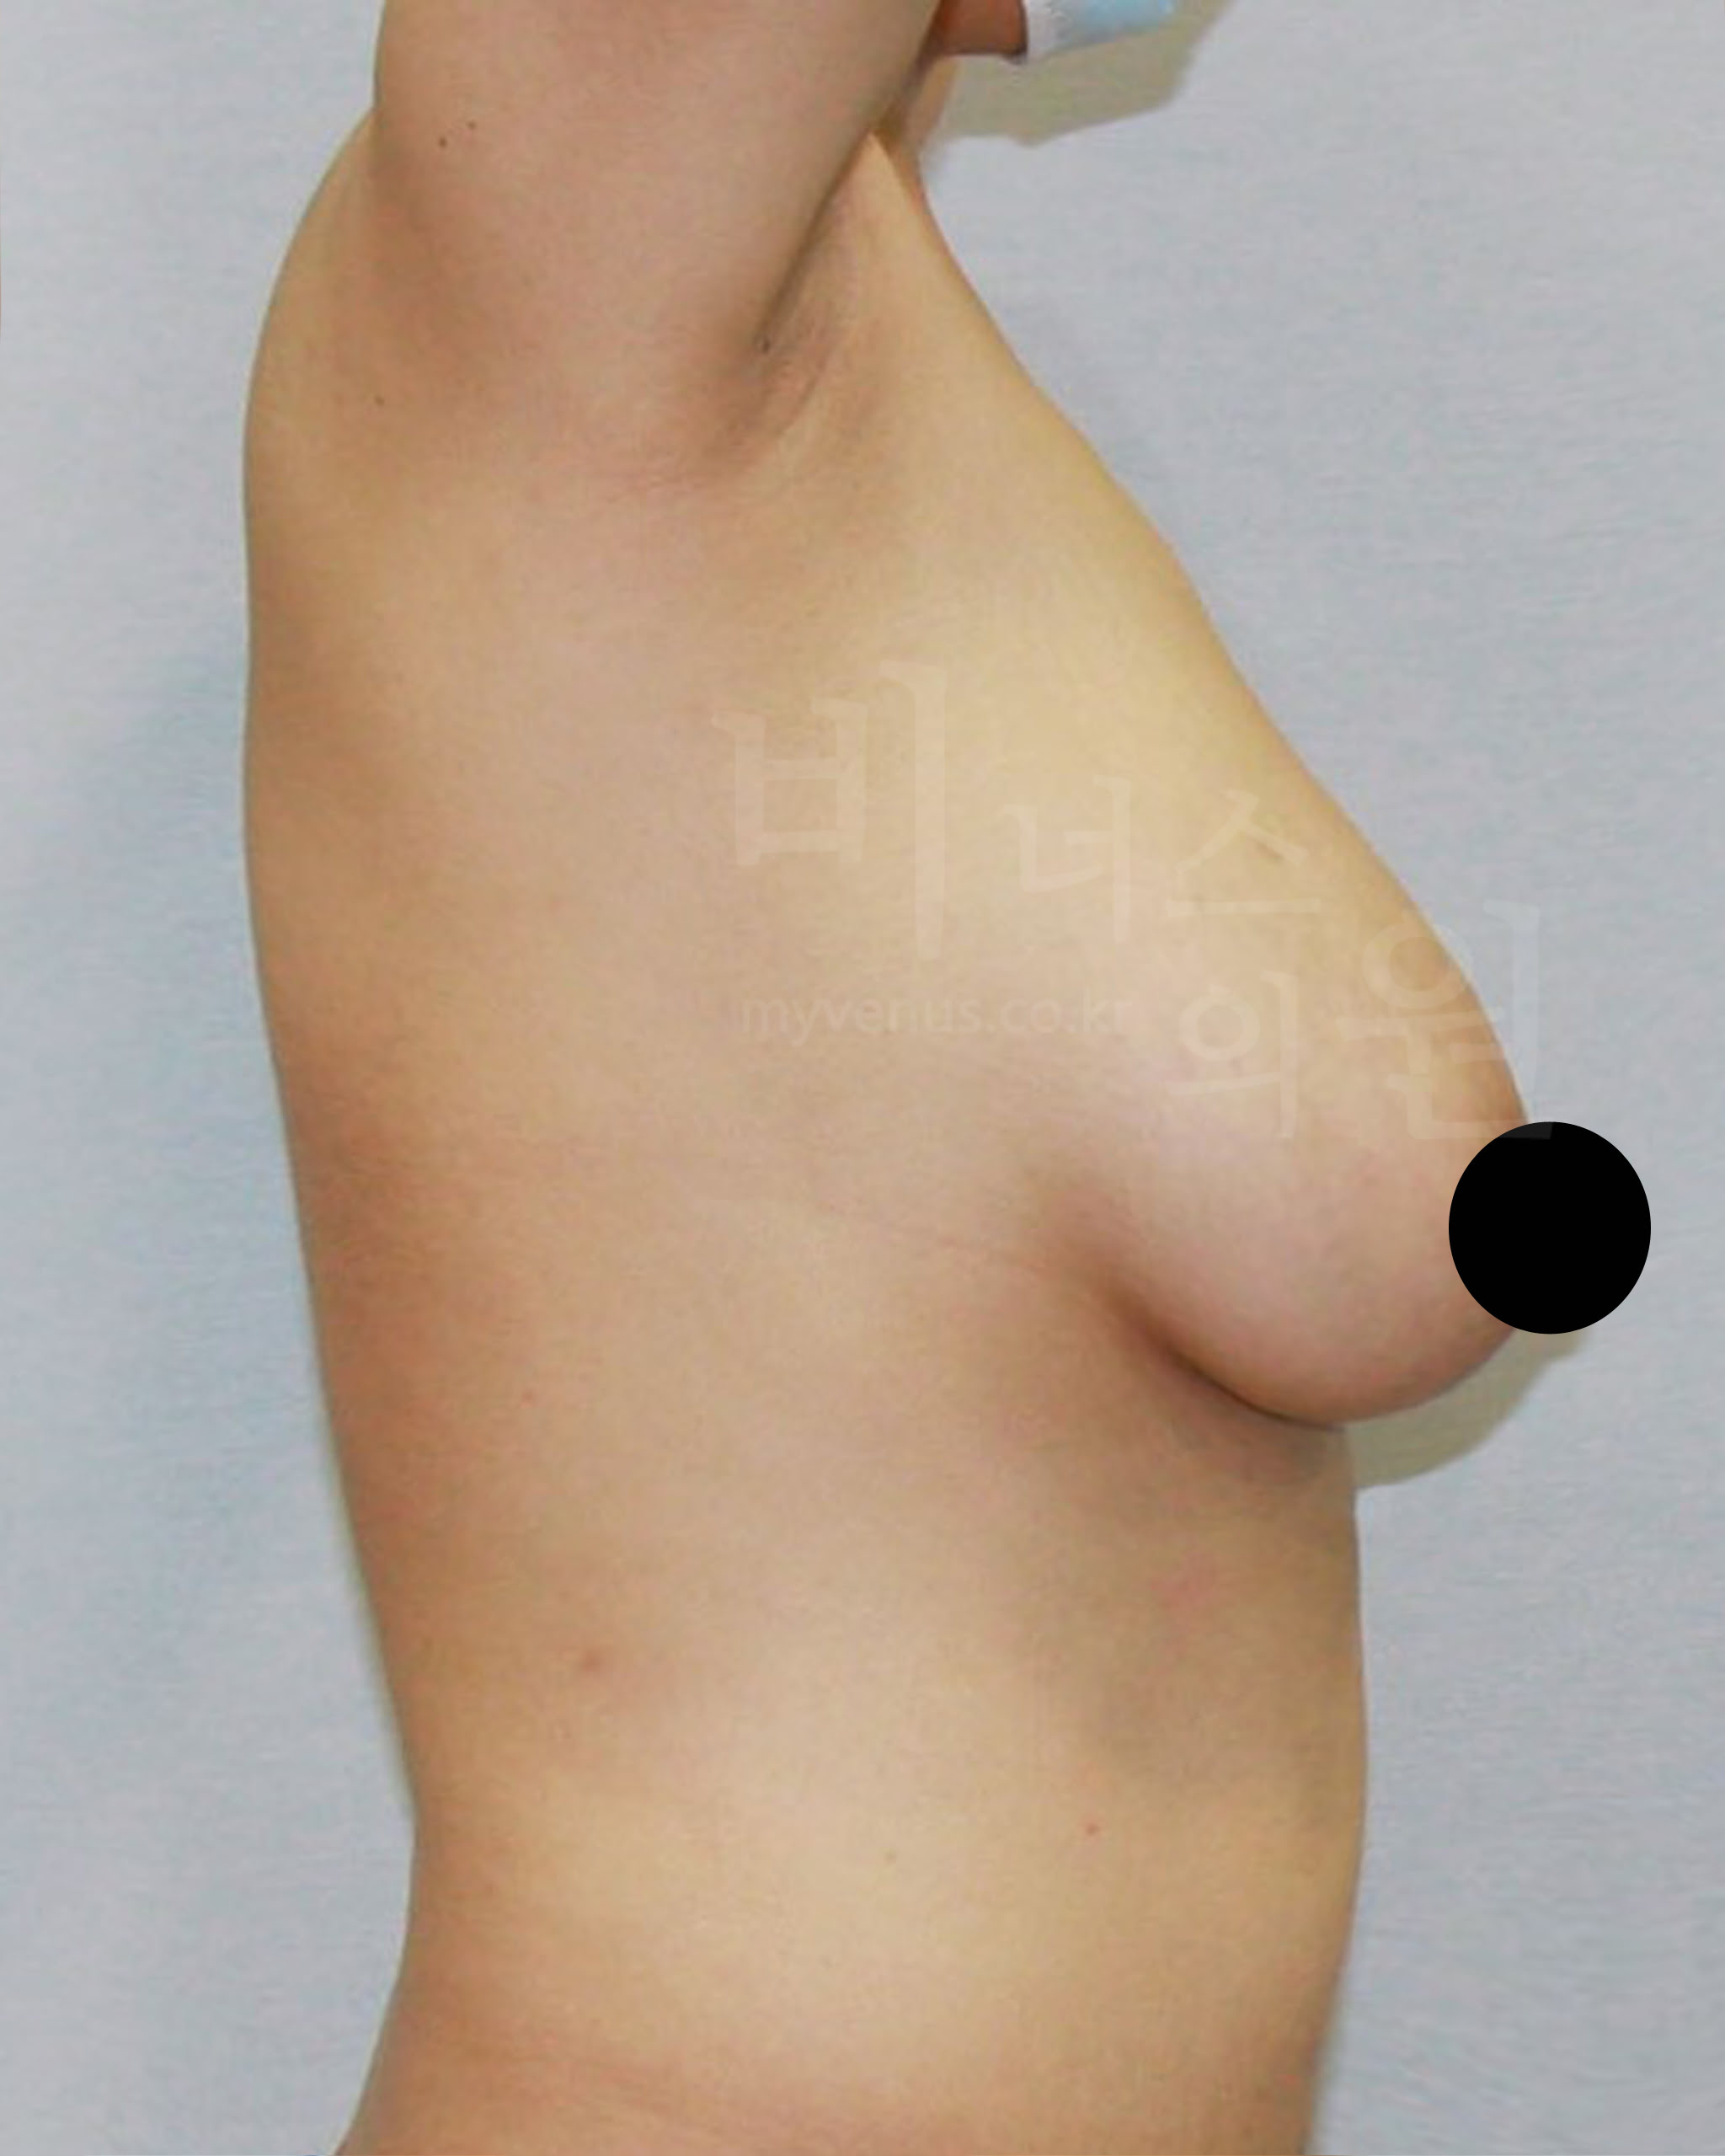

가슴축소 지방흡입 전, 한달 후 경과 사진으로 보는 효과

수술 부위 - 가슴 축소, 부유방, 겨드랑이, 유방 옆구리 지방흡입

가슴축소 지방흡입 전 사진

유방이 처지고 몸에 비해 큰 가슴 모습

가슴축소 지방흡입 후 사진

처짐 없이 사이즈가 감소와 리프팅 된 모습

젊은 여성분으로 무겁고 처진 가슴의 사이즈 감소를 위해 내원해 주셨어요. 가슴축소 지방흡입 후 가슴 사이즈가 주었으며, 처짐 없이 볼륨 업 된 가슴을 확인할 수 있어요. 가슴뿐만 아니라 부유방, 겨드랑이, 유방 옆구리 지방흡입을 함께 함으로써 주변 부위와 어색함 없어요.

가슴축소 지방흡입 전 사진

처진 정도가 유방 길이로 보여지는 모습

가슴축소 지방흡입 후 사진

사이즈 감소와 유방 길이가 짧아진 모습

가슴축소 지방흡입은 저렴한 비용으로 흉터나 수술 후의 부작용, 합병증 걱정 없이 큰 가슴의 고통에서 벗어나 볼륨 있고 예쁜 가슴을 만들 수 있어요. 측면의 모습에서 가슴 안쪽의 유방 선이 길게 늘어져 있던 모습이였으나 처짐 없이 볼륨 업된 사이즈 감소가 이루어지면서 가슴 선이 짧아 졌어요.